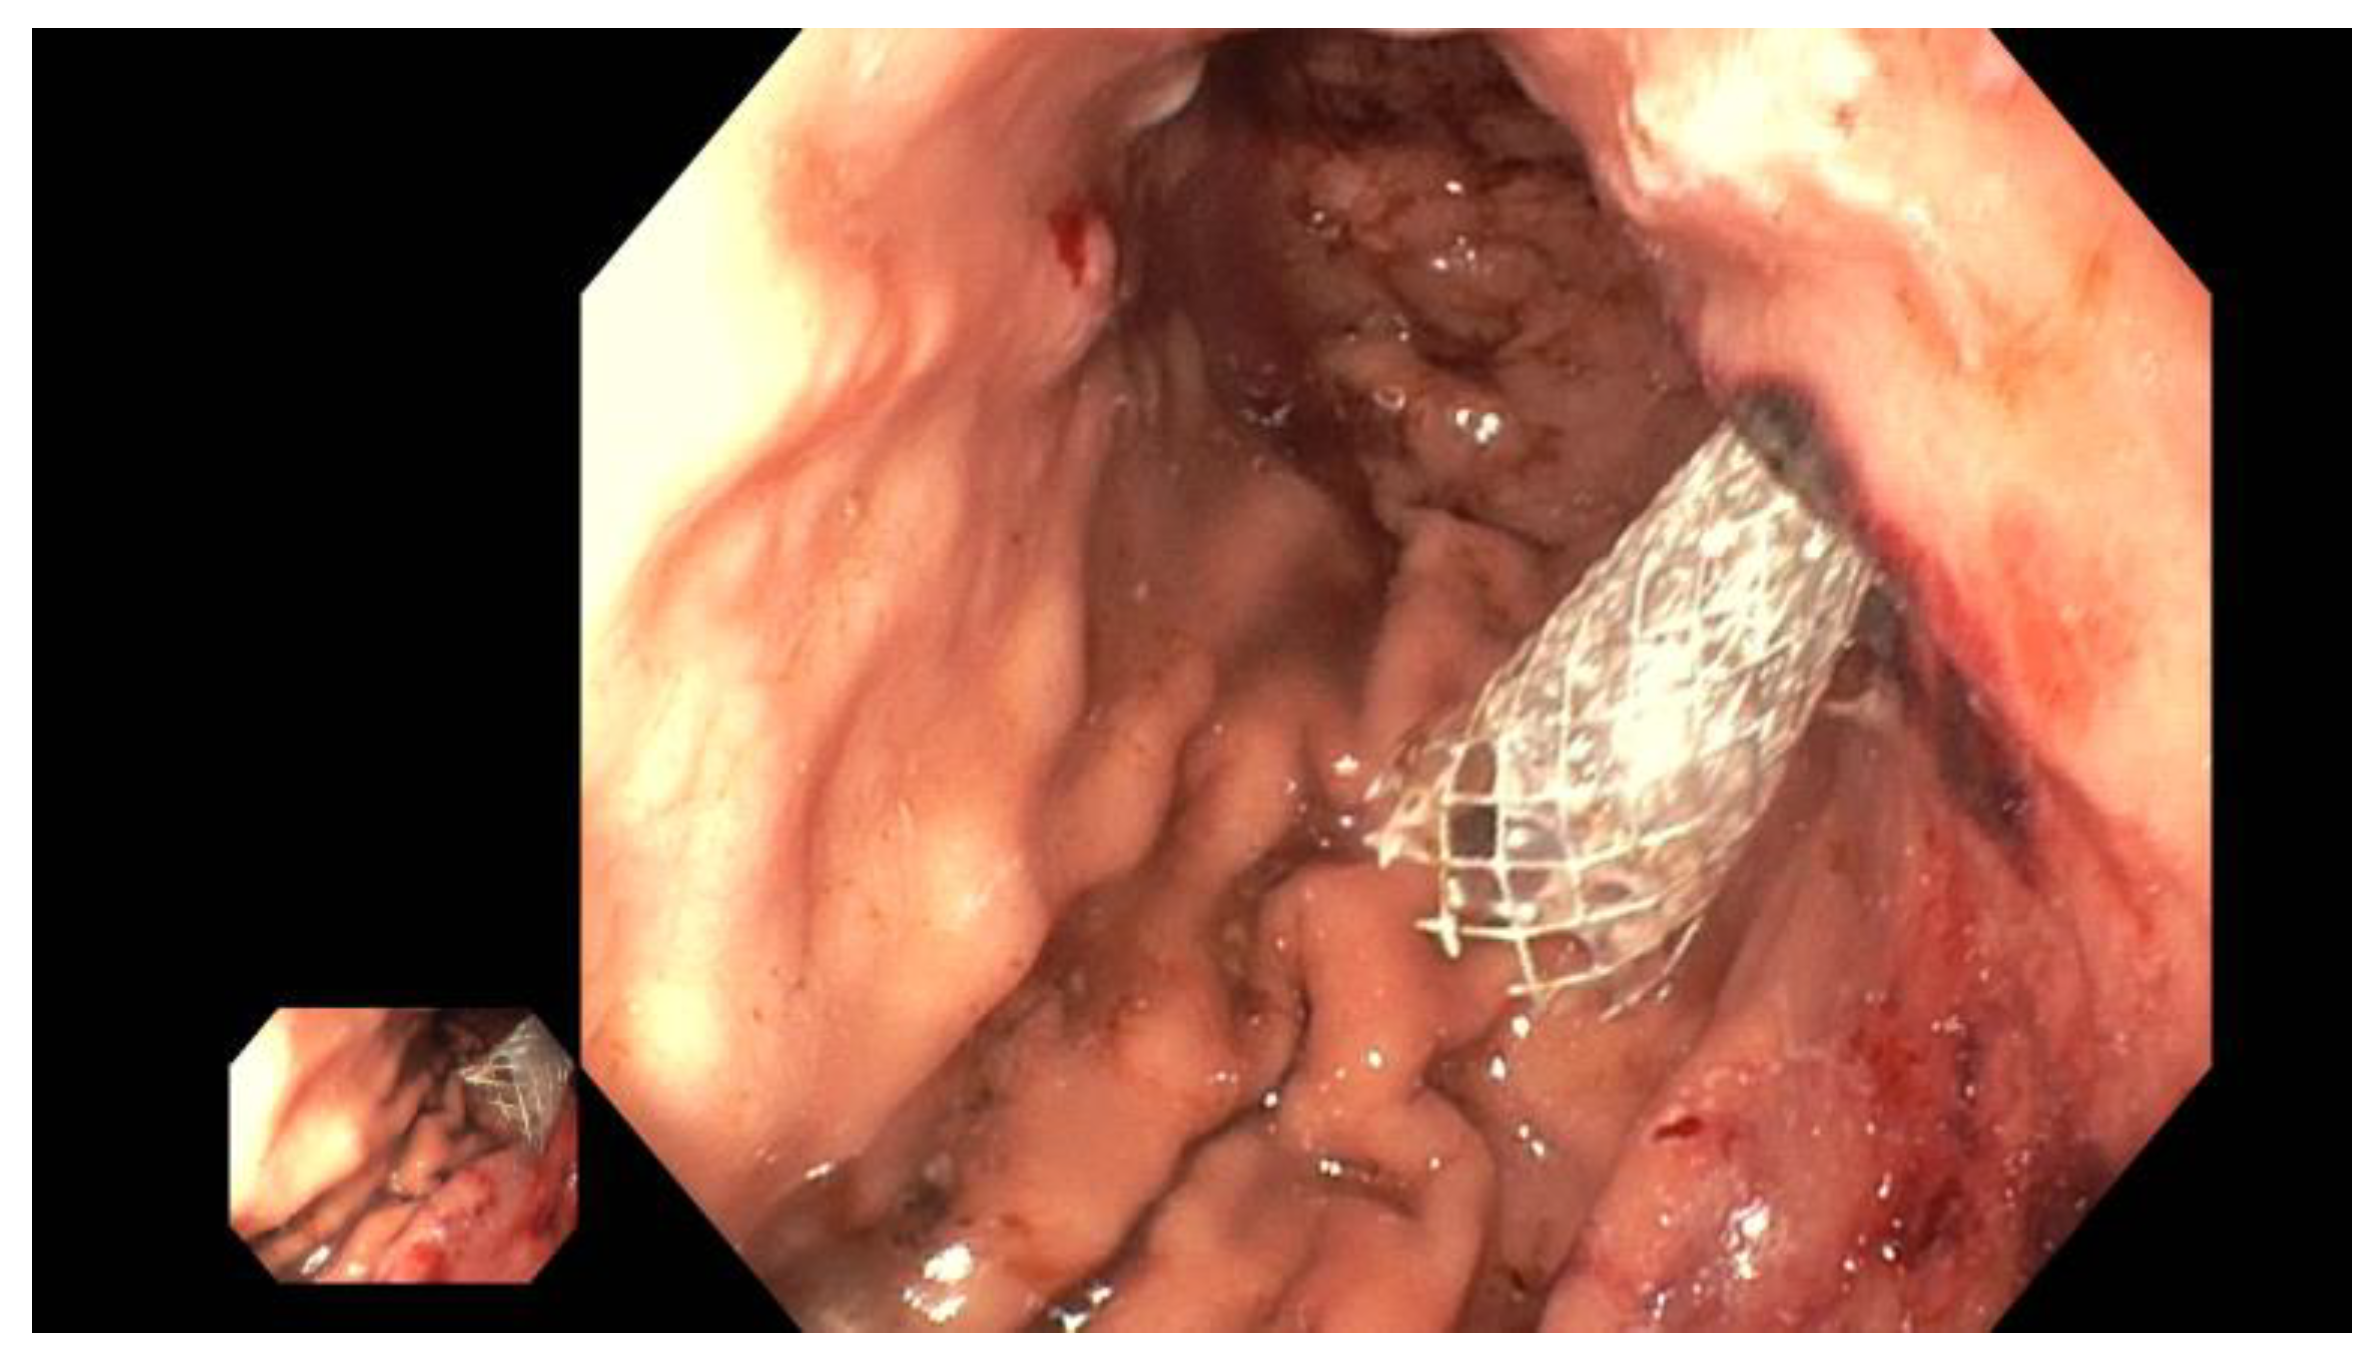

The advantage of using a metal stent (such as Hanaro® by Olympus, Hamburg, Germany, or SEM by Boston, Ratingen, Germany) lies in the possibility of later transmural targeted intervention in the pancreatic duct with a pancreaticoscope (such as SpyGlass by Boston Scientific, Ratingen, Germany). This option should be considered if primarily impassable strictures or obstructing pancreaticoliths are suspected, as these can be treated via targeted visual inspection. Pancreaticoliths, for example, can be fragmented and removed using pancreaticoscopic electrohydraulic lithotripsy (EHL), thereby restoring physiological antegrade drainage (Figure 8).

(C) EUS-guided internal antegrade pancreatic duct drainage: In cases where the papilla or anastomosis cannot be accessed, a wire is inserted following the puncture of the pancreatic duct. Subsequently, an HF ring knife (MTW Endoskopie Manufaktur W. Haag KG, Wesel, Germany) is introduced via the wire, which can also be employed to overcome challenging strictures with specialized wires, as there is no risk of wire ablation. If the stricture at the anastomosis can be passed, an 8- to 15-mm dilatation balloon is inserted to dilate the stenosis (refer to Figure 9). Additionally, a long pigtail (14 cm, 8.5 French) can be inserted as jejuno-pancreatico-gastrostomy (ring drainage) to secure the dilatation effect, which can be removed after approximately 8–12 weeks.

Figure 9. Post-pancreatojejunostomy resection—remitting pain—dilated pancreatic duct; transgastric puncture of the pancreatic duct—demonstration of a pancreaticolith (red arrow, to the anastomotic stenosis (left panel); balloon dilation (red arrow) of the stenosis, advancement of the stone in push technique (middle panel); placement of jejuno-pancreatico-gastrostomy drainage (red arrows; 8.5-Fr. double pigtail); right panel (satellite panel, endoscopic control view), selected from the clinical picture library of the reporting Dept. of Gastroenterology, Hepatology and General Internal Medicine.